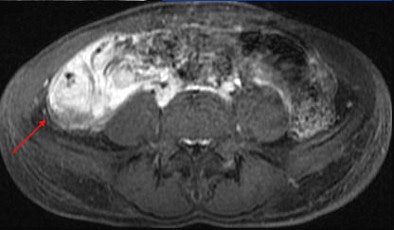

MRI results were then compared to colonoscopy and pathology reports to determine the presence or absence of disease in evaluable bowel segments. Individual imaging parameters (including wall thickening, enhancement, T2 signal, mesenteric vascular prominence, and adenopathy) were also separately analyzed to determine their independent predictive value, the authors wrote.

The study team acquired steady-state free-precession (SSFP) images of the abdomen and pelvis (TR= 4 ms, TE = 2 ms, slice thickness 8 mm for coronal images and 8-mm for axial images). Axial and coronal fat-suppressed half-fourier single-shot fast-spin echo (SSFSE) and axial spoiled-gradient images were also obtained through the abdomen, followed by T1-weighted fat-suppressed spoiled-gradient echo (LAVA/VIBE) images, before the injection of 1 mmol/kg of gadopentate dimeglumine contrast (Bayer Healthcare) followed by a saline flush and postcontrast imaging.

A single experienced abdominal radiologist, blinded to the final results, interpreted all of the MRE images, rating wall thickness, abnormal enhancement, abnormal T2 signal, and mesenteric vascular prominence on a scale of 1-4. All endoscopy reports were reviewed for mention of inflammatory changes in specific bowel segments, and pathology reports were reviewed for the presence of inflammatory disease, the study team reported.

Mild pathologic changes are more difficult to detect with MRE or any other imaging test compared to severe changes, the authors wrote. Thus, the sensitivity of MRE for detection of pathologically mild disease was 68% in the terminal ileum and 27% in the colon, versus 87% in the ileum and 88% in the colon for severe disease. The negative predictive value of MRE was 89% for distal ileal disease and 96% for colonic disease, "indicating that MRE may successfully exclude active Crohn's disease," Grand and colleagues stated.

Interestingly, the results were in line with smaller studies that used antiperistaltic agents, they wrote. As in those studies, MRE showed its real strength in a couple of features of active Crohn's disease. "Analysis of individual MR parameters demonstrates that wall thickening and abnormal enhancement are the most sensitive indicators of Crohn's disease on MRE while abnormal T2 signal, mesenteric vascular engorgement, and adenopathy were insensitive but specific," he wrote.